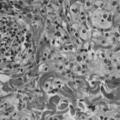

Microscopic

Features:[4]

- Foamy histocytes.

- Large cells with gray, bubbly cytoplasm.

- +/-Touton giant cells - very distinctive histiocytes - classic.

- Nuclei form a ring around the cell periphery.